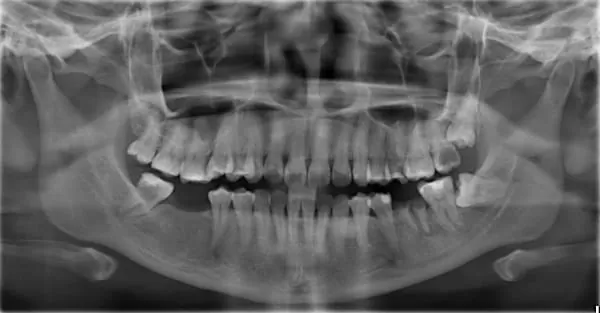

(圖1) 傳統平面X光片無法顯示立體的影像

隨著國人口腔衛生意識抬頭及國外人工植牙的成功與進步,近年來台灣接受人工愈多,但傳統平面X光片無法顯示立體的影像(圖1),不足以精準判斷缺牙位置的骨質寬度及密度,所以植牙前皆需拍攝電腦斷層( Computerized Tomography,簡稱CT),CT讓醫師能準確判斷及評估,是牙科極具代表性,卻也是相當昂貴的設備之一,目前也不是每家診所都能有此項設備。